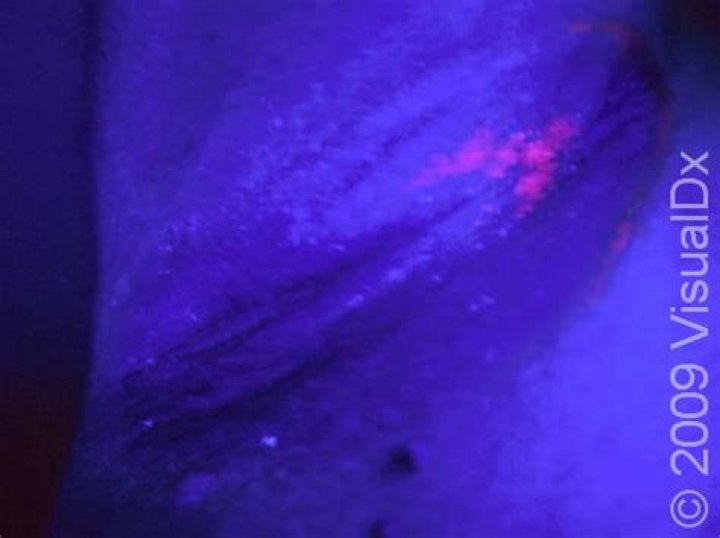

What does fungus look like under a blacklight?

These areas will have sharper borders under black light and will look bright blue-white or yellow-green. Ringworm. Like tinea capitis, ringworm, or tinea corporis, is a skin infection caused by a fungus. It's a red, itchy, circular rash that gets its name from its appearance.

What color is ringworm under black light?

Using light is a simple way to detect ringworm, although not the only way. The color of ringworm under a Woods Lamp is a bright apple green, which may show under a blacklight with a blue filter in a darkened room.